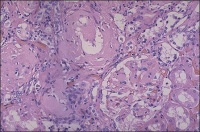

肾淀粉样变性活检片

4.确诊有赖于脏器的活体组织检查,如肝、肾、直肠黏膜活检。刚果红试验有助于诊断。